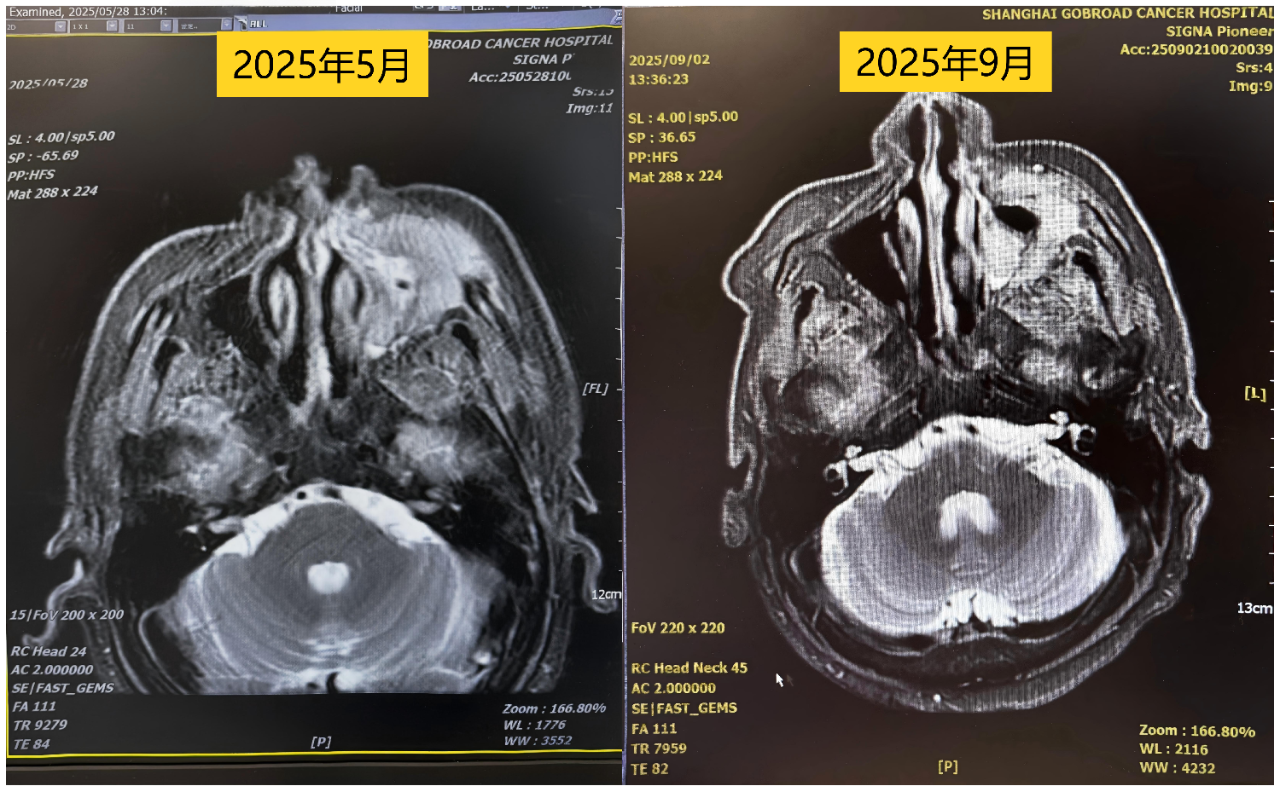

“去分化脂肪肉瘤对化疗相对敏感,术前化疗的目的是缩小肿瘤、降低分期,为手术完整切除创造条件。”姚阳教授解释道。经过5次化疗,影像学评估显示肿瘤部分缓解(PR)——这意味着,手术时机成熟了!

5次化疗后肿瘤缩小评估:局部PR